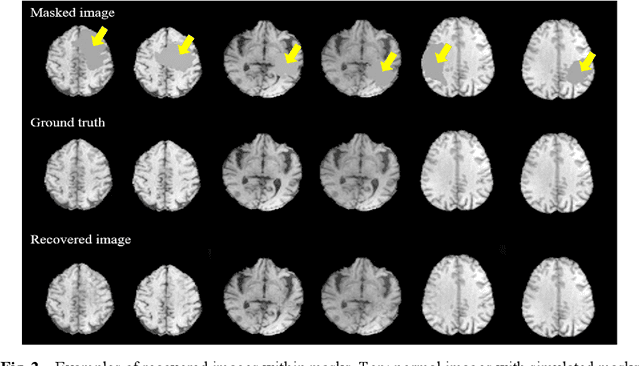

Abstract:In brain tumor diagnosis and surgical planning, segmentation of tumor regions and accurate analysis of surrounding normal tissues are necessary for physicians. Pathological variability often renders difficulty to register a well-labeled normal atlas to such images and to automatic segment/label surrounding normal brain tissues. In this paper, we propose a new registration approach that first segments brain tumor using a U-Net and then simulates missed normal tissues within the tumor region using a partial convolutional network. Then, a standard normal brain atlas image is registered onto such tumor-removed images in order to segment/label the normal brain tissues. In this way, our new approach greatly reduces the effects of pathological variability in deformable registration and segments the normal tissues surrounding brain tumor well. In experiments, we used MICCAI BraTS2018 T1 tumor images to evaluate the proposed algorithm. By comparing direct registration with the proposed algorithm, the results showed that the Dice coefficient for gray matters was significantly improved for surrounding normal brain tissues.